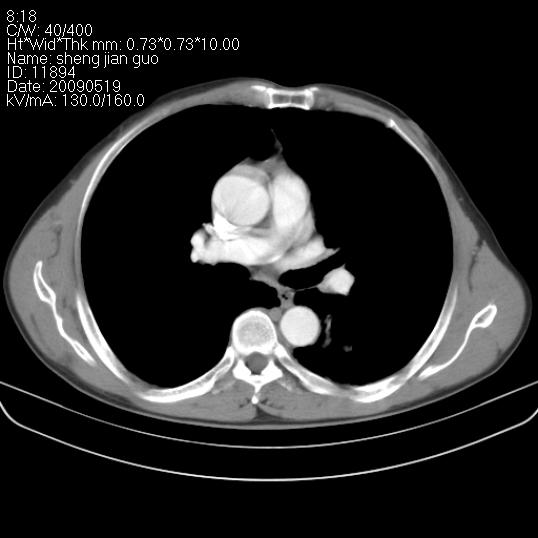

以下是引用zjzjr在2009-5-19 17:25:00的发言:[br]支持楼主考虑,另左肺下叶阻塞性炎症。

以下是引用zhao_bin2008在2009-5-19 17:48:00的发言:[br]支持左肺下叶周围型肺癌并阻塞性肺炎。

以下是引用zsl6918在2009-5-20 7:10:00的发言:[br]左侧中心型肺癌!